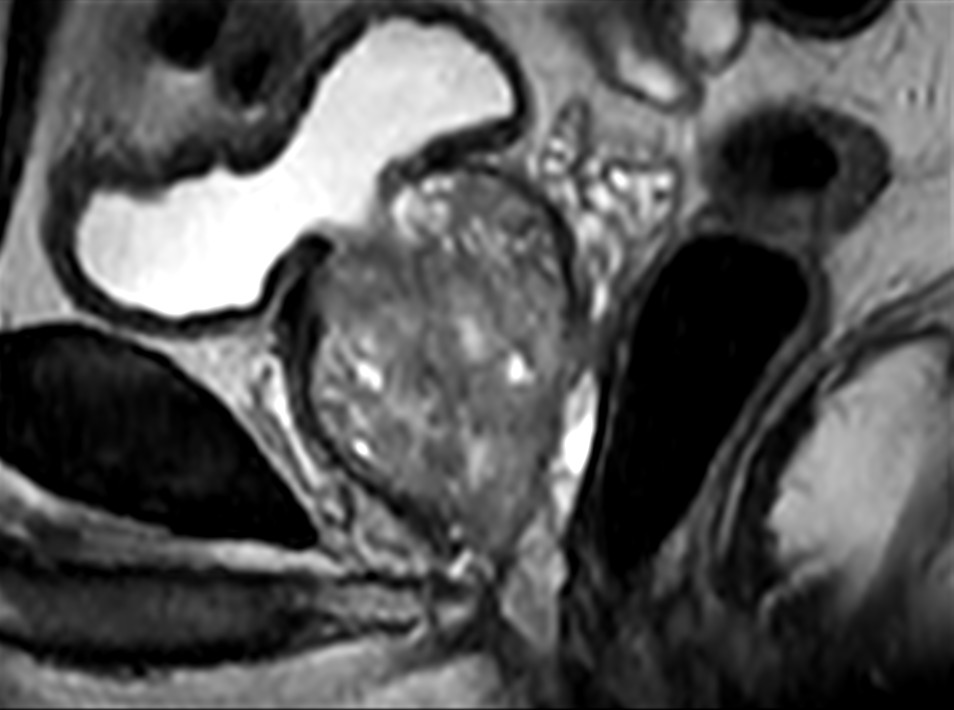

Fast Prostate imaging with SmartSpeed Precise

Kumamoto Chuo Hospital Japan